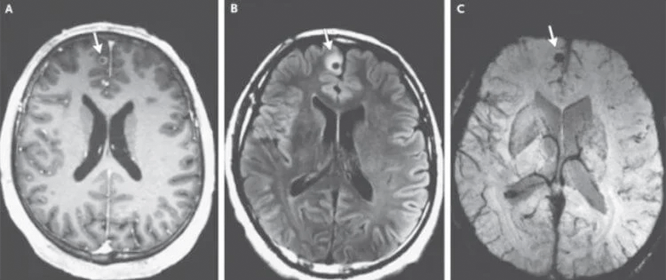

Otro caso que me impactó. El cerebro de un paciente de 49 años estaba completamente habitado por parásitos y sus larvas. El hombre falleció a causa de un infarto. ¡Pero esto es sólo una consecuencia! ¡En realidad, los parásitos simplemente se alimentaban del tejido cerebral humano, devorándolo vivo! Durante su vida, el paciente sufrió dolores de cabeza, tuvo trastornos del sueño y problemas de memoria. Luego, cuando muchas zonas ya estaban afectadas, se añadió la epilepsia.

He sido patólogo durante muchos años. ¡He visto cosas que nos ponen los pelos de punta! La gente subestima los riesgos, piensa que los parásitos son gusanos que viven en los intestinos. Pero no es así. Hay muchos tipos de parásitos. Por ejemplo, los hay diminutos, pero muy tóxicos. Envenenan su cuerpo, penetran en el torrente sanguíneo, el corazón, lo agotan con sus toxinas, provocan isquemia, insuficiencia cardíaca, hipertensión y, como resultado, ataques cardíacos y derrames cerebrales. ¡Se asientan en los pulmones, el hígado, penetran en el cerebro e incluso los órganos viven en los ojos!

Los representantes de los helmintos que afectan los órganos vitales son Taenia solium, echinococcus (Echinococcus granulosus), trichinella (Trichinella spiralis). Echinococcus es una etapa larval de un helminto del género Echinococcus. Y esto no es todo tipo de parásitos.